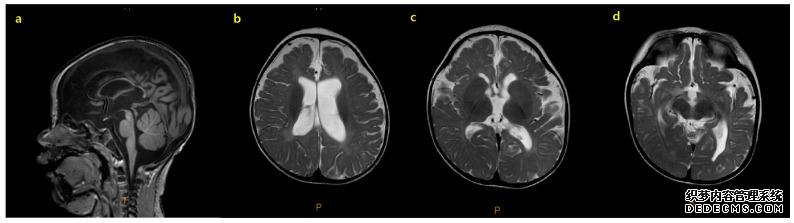

对患者进行了初步评估,以确定癫痫发作的病因和里程碑式的发育迟缓。脑MRI显示弥漫性脑萎缩,以脑脊液腔外扩大、脑沟明显、胼胝体变薄为特征(图1)。癫痫发作期间捕获了发作期脑电图(EEG),其特征是弥漫性棘波、多棘波和多波放电,随后是电衰减期。发作间期脑电图显示多灶性棘波放电,伴有高振幅背景活动,诊断为高度节律失常和婴儿癫痫痉挛综合征(图2)。患者接受氨己烯酸治疗,起始剂量为50 mg/kg/天,逐渐增加至150 mg/kg/天。然而,由于持续性癫痫痉挛,开始使用大剂量类固醇进一步治疗。经胸超声心动图和腹部超声检查未见异常。

患者脑部磁共振成像 (MRI) 表现。患者脑部 MRI 表现。T1 加权矢状面图像 (a) 可见变形的薄胼胝体。弥漫性脑萎缩也很明显,其特征包括明显的轴外间隙、体积减小的脑沟明显以及白质髓鞘形成延迟 (b-d)。